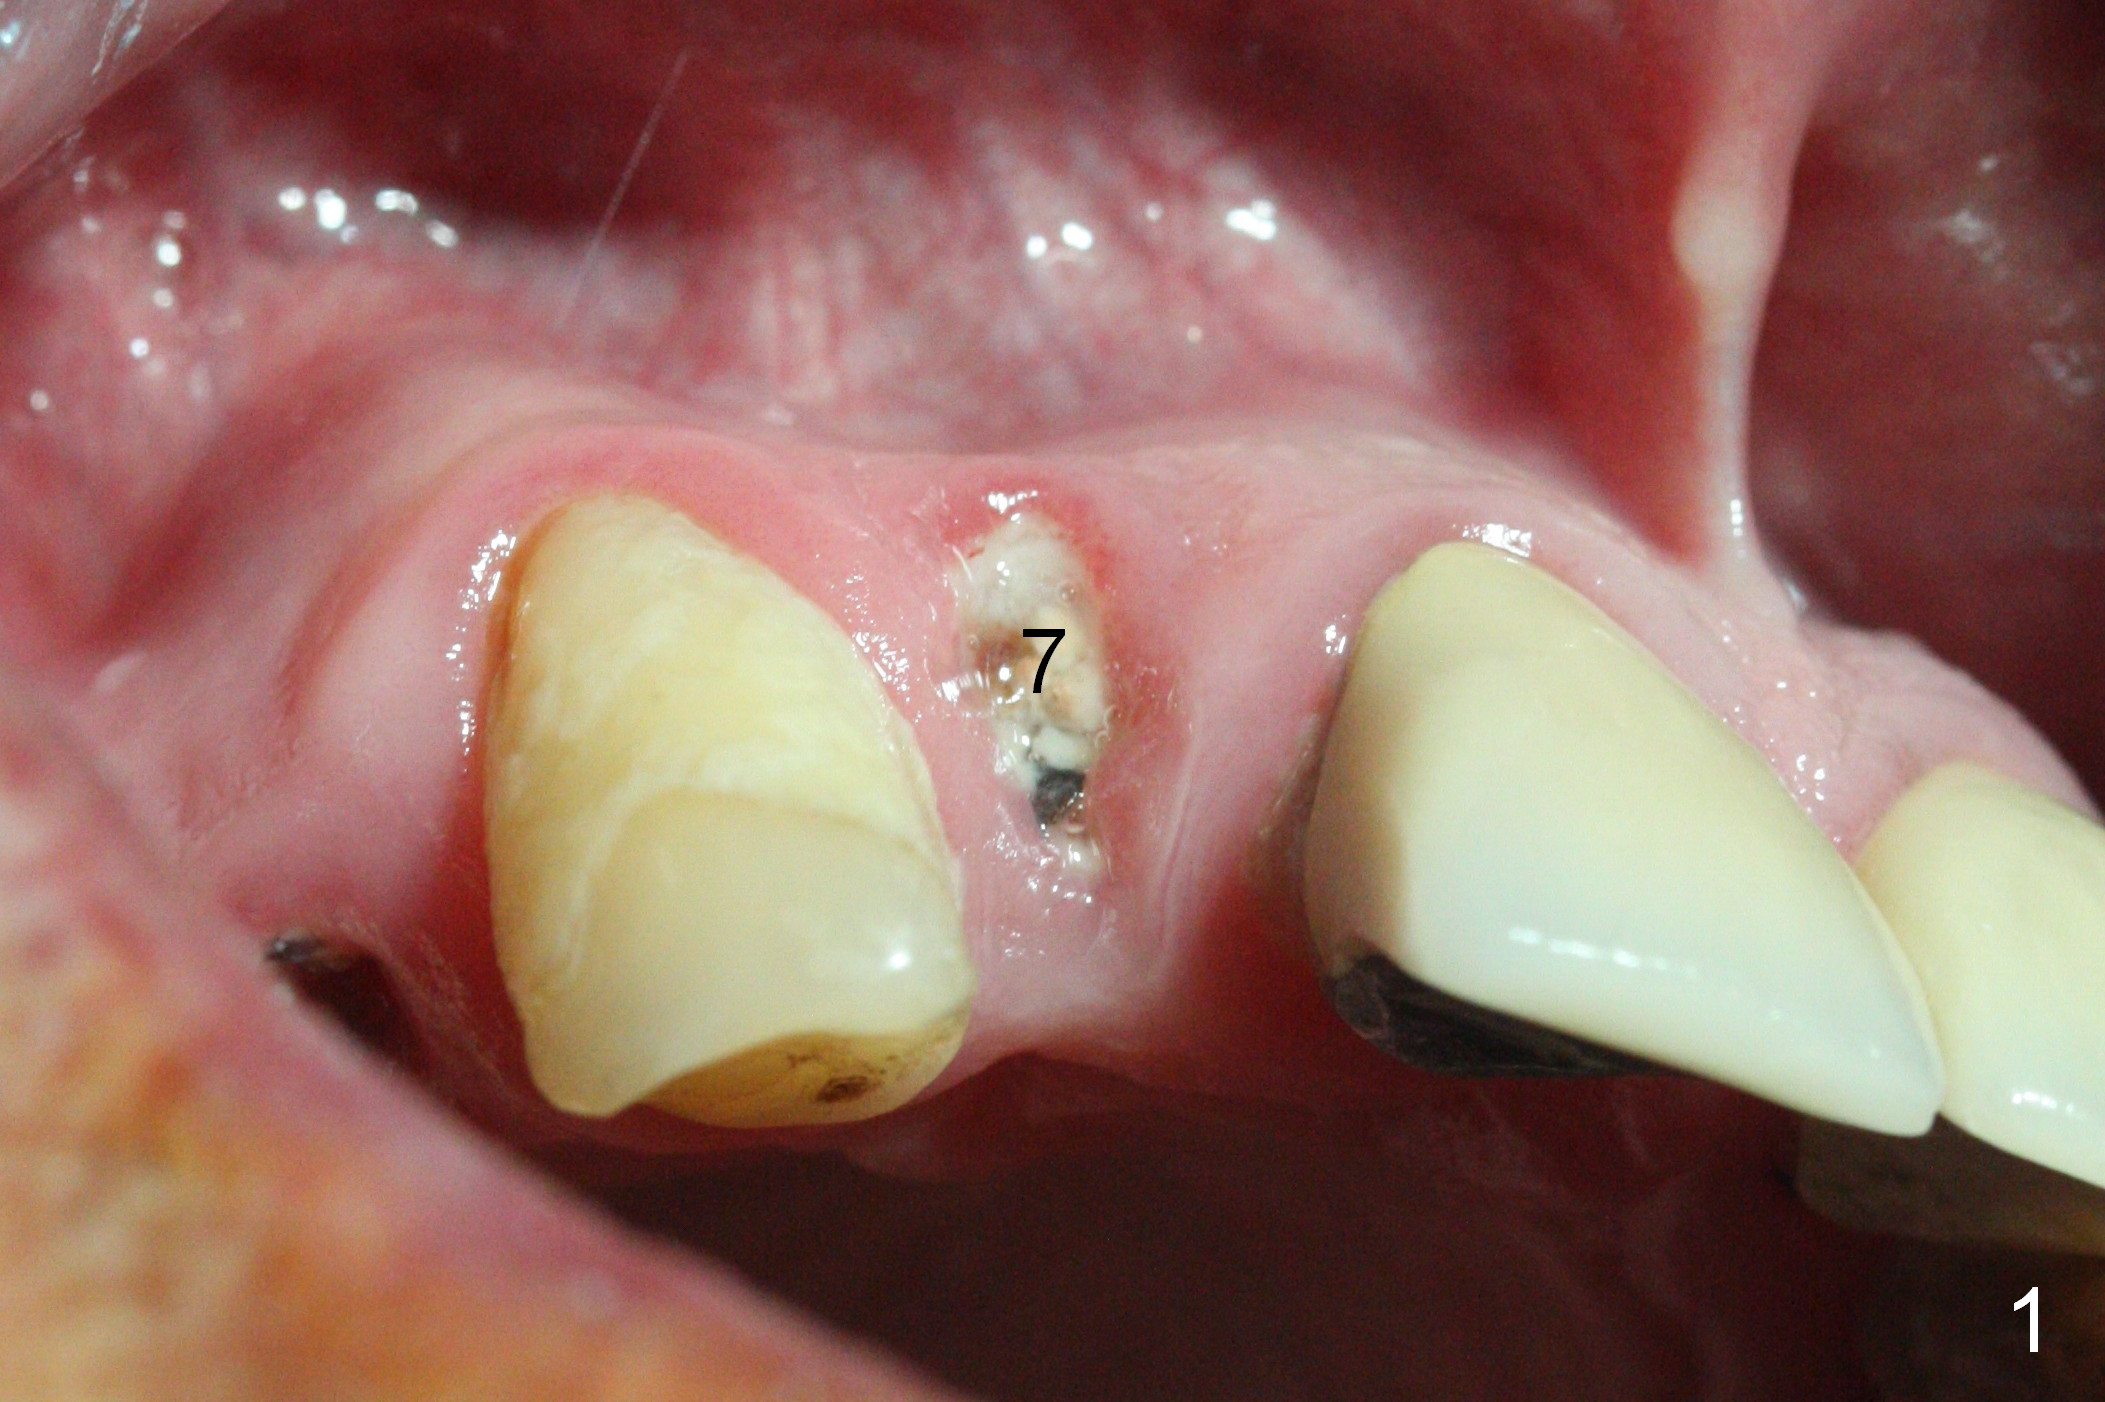

The residual root at #7 is fairly well exposed with buccal gingival recession (Fig.1). The implant placement is flapless (Fig.2-7). What is not shown is that the 3.8x13 mm implant is buccally subcrestally placed (Fig.3). After 1st round of bone graft buccal to the implant, a 4.5x5(5) mm abutment is immediately placed and prepared (Fig.4,5). An immediate provisional is placed after 2nd round of bone graft subgingivally buccally (Fig.6,7). Note the bulging gingiva (*), as compared to that in Fig.4,5. The long implant is chosen because of anterior deep bite (Fig.4) and lack of posterior support (Fig.7).